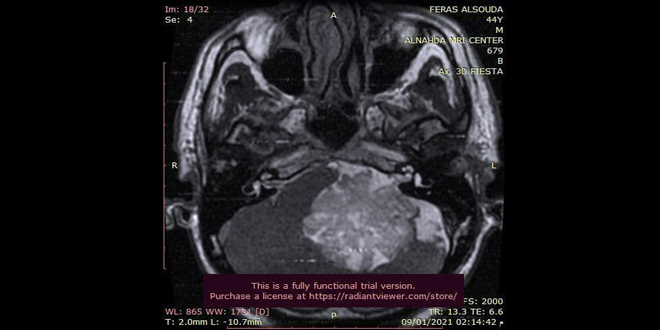

وفي تصريح لـ سانا أوضح الدكتور سليم أن العمل الجراحي الذي أجري الأسبوع الماضي واستغرق عشر ساعات أنقذ حياة مريض في الأربعين من عمره يعاني منذ نحو 8 سنوات من ورم سليم حجمه 6-7 سم يقع في الزاوية الجسرية المخيخية وهو من الأورام النادرة لجهة الحجم ومكان التوضع وتتراوح نسبة حدوثه عالمياً بين الأورام الدماغية من 0.5 إلى 2 بالمئة على مستوى العالم ويفسر حدوثه بأنه ورم خلقي ازداد حجمه مع مرور الوقت.

ووفق الجراح الشاب كان المريض قبل استئصال الورم يعاني حالة صحية سيئة ووصل إلى مرحلة عدم القدرة على الأكل أو المشي وفقدان حاسة السمع مع صداع وإقياء دائم معتبراً أن ذلك نتيجة طبيعية بسبب وجود الورم بمكان مرور الأعصاب المسؤولة عن حاسة السمع وعملية البلع وحركة الوجه وتشكيله ضغطاً كبيراً على الأعصاب القحفية وهي المحرك الأساس لتنظيم الضغط والنبض والأكسجة.

وأجري العمل الجراحي كما أوضح الدكتور سليم على مرحلتين الأولى تصريف السائل الدماغي الشوكي من الرأس إلى البطن والثانية استئصال الورم من المخيخ وتحرير الأعصاب وتمت الجراحة باستخدام المجهر ببعض المراحل والتنظير بمراحل أخرى.

ولفت الدكتور سليم إلى أن صعوبة استئصال هذا النوع من الأورام تكمن بتجنب إحداث أي أذية للأعصاب أو الشرايين التي يتوضع عليها الورم مؤكداً أن المريض تخرج من المشفى بحالة صحية جيدة وبدأ باستعادة حياته بالشكل الطبيعي تدريجياً.